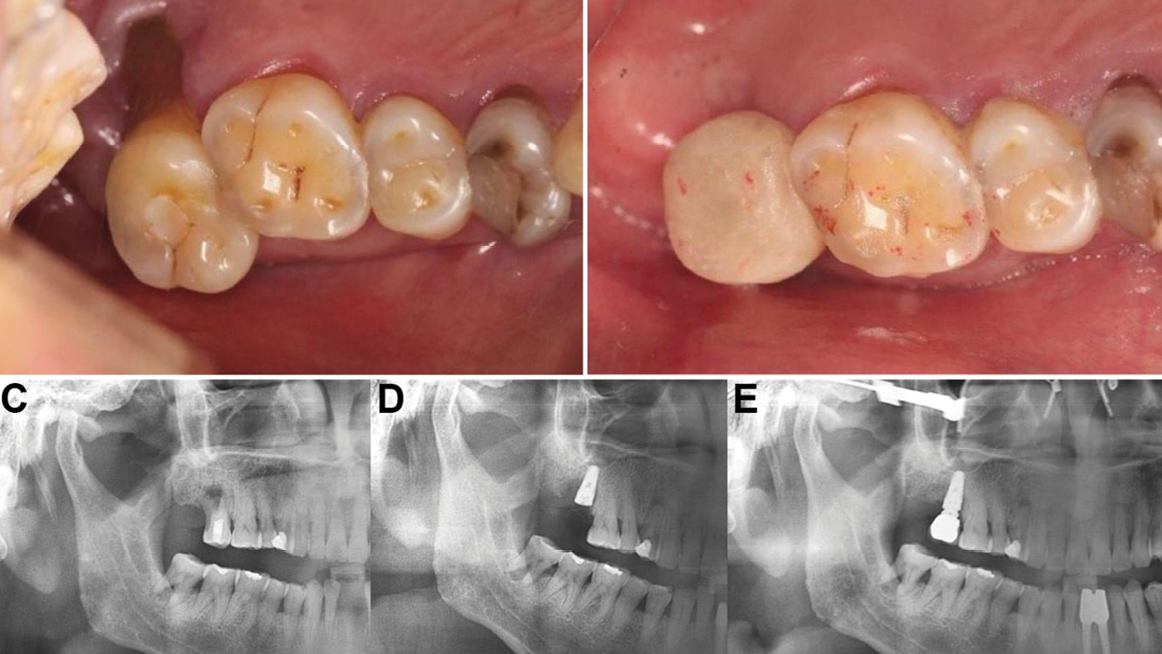

Fracture of dental implants with internal, conical connections: A case series

Deporter-Fig_1D alternate text for this image

Abstract Purpose: Fracture of dental implants, though uncommon, presents significant clinical consequences. The case reports presented explore the fracture of four dental implants in three patients. All were of the Astra Osseospeed® design with internal conical connections. All fractured at the level of the prosthetic connection, providing insight on potential contributing factors. Methods: Three patients all received … Read more